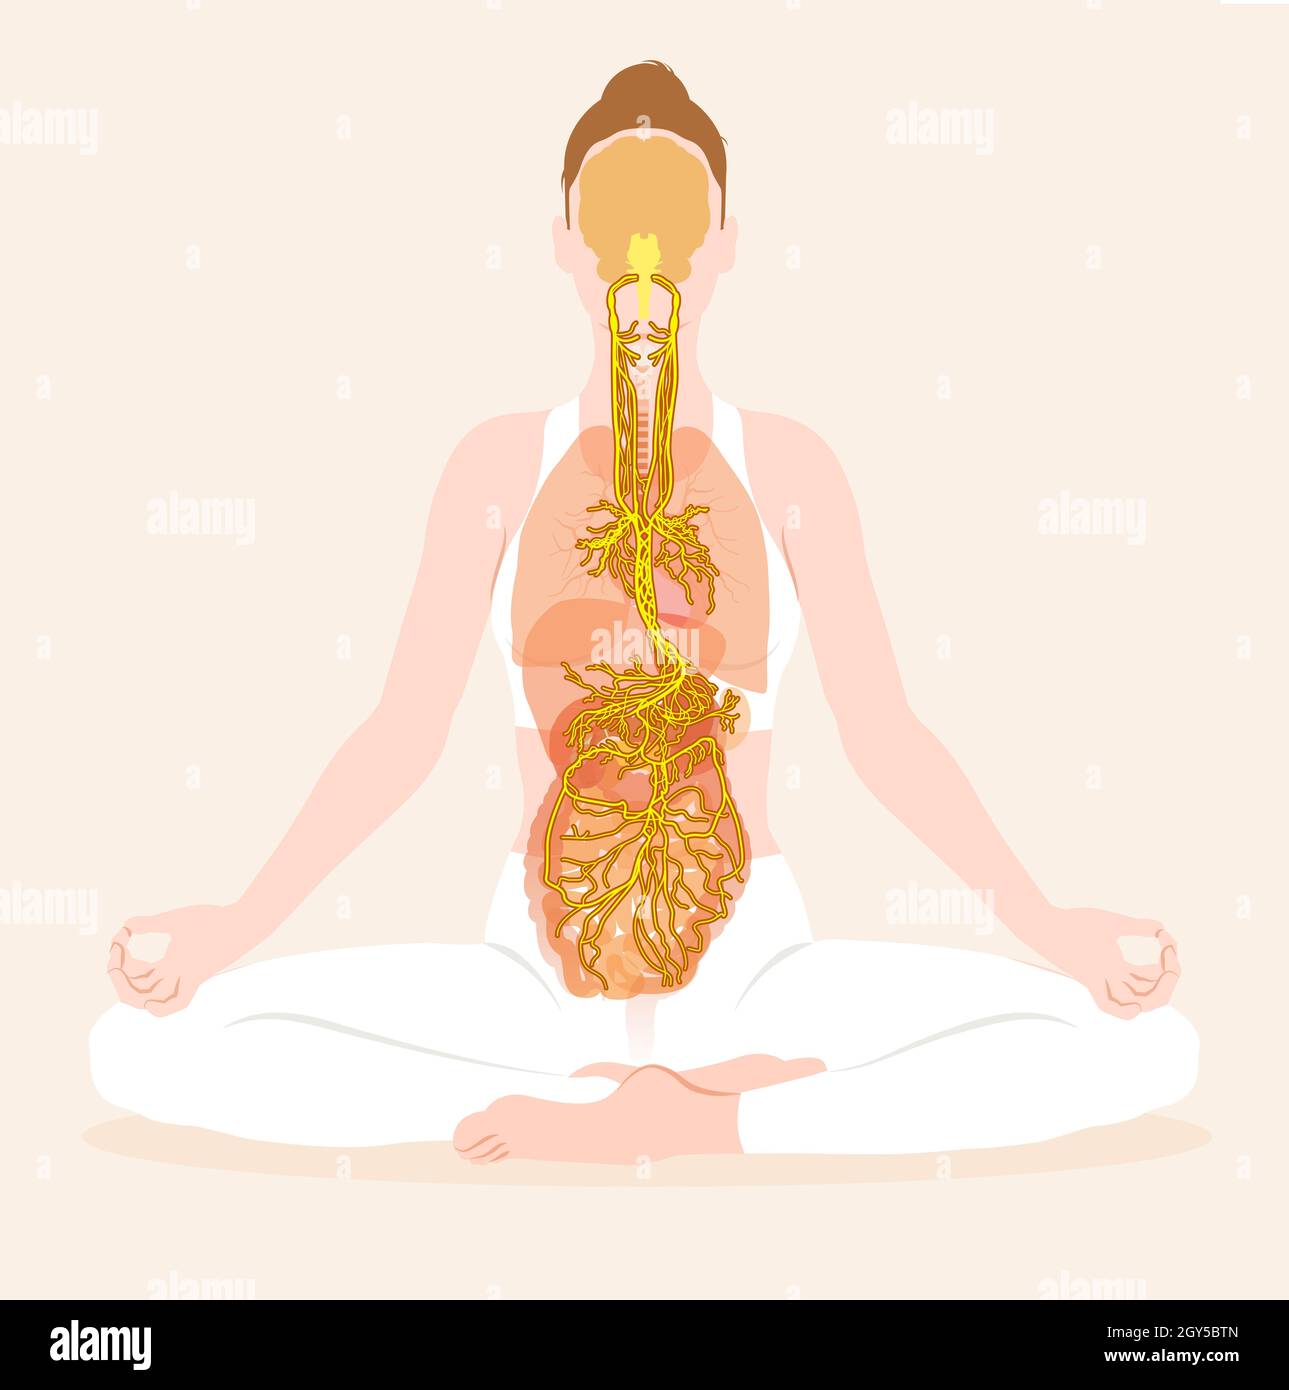

This illustration showing brain and active vagus nerve (tenth cranial nerve) with lungs, heart, stomach and digestive tract Stock Photohttps://www.alamy.com/image-license-details/?v=1https://www.alamy.com/this-illustration-showing-brain-and-active-vagus-nerve-tenth-cranial-nerve-with-lungs-heart-stomach-and-digestive-tract-image446973989.html

This illustration showing brain and active vagus nerve (tenth cranial nerve) with lungs, heart, stomach and digestive tract Stock Photohttps://www.alamy.com/image-license-details/?v=1https://www.alamy.com/this-illustration-showing-brain-and-active-vagus-nerve-tenth-cranial-nerve-with-lungs-heart-stomach-and-digestive-tract-image446973989.htmlRF2GY5BTN–This illustration showing brain and active vagus nerve (tenth cranial nerve) with lungs, heart, stomach and digestive tract